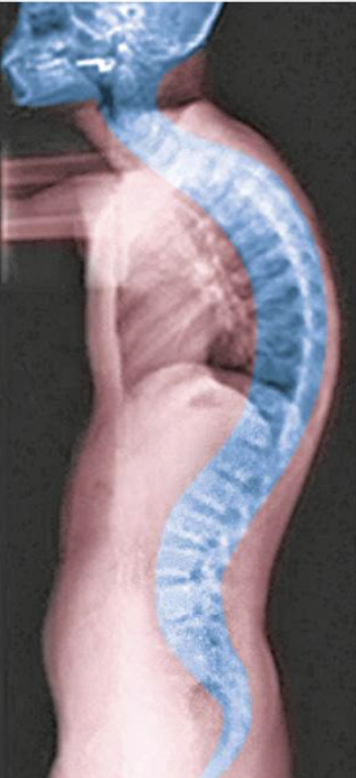

lordosis

Exaggerated cervical or lumbar curvature

Happens when a lot of weight is pushed on vertebral

Ex. pregnancy

kyphosis

Exaggerated thoracic curvature

Ex. hunch back